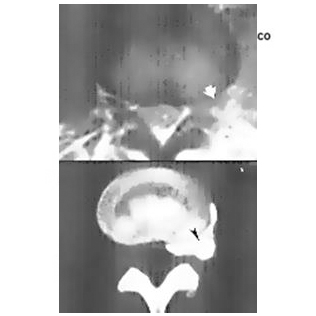

Las radiografías son útiles, pero una tomografía axial computarizada (TC) o imágenes por resonancia magnética (IRM) brindan más detalle. La IRM es el mejor método para permitirle al médico ver los tejidos espinales blandos que no se pueden ver en una radiografía convencional.

Evidencia radiográfica de HNP